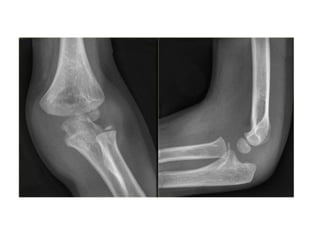

Supracodylar fracture –common and most serious fractures in childhood Mechanism- Fracture is caused by a fall on an out-stretched hand. As the hand strikes the ground, the elbow is forced into hyperextension resulting in fracture of the humerus above the condyles. Extension- Distal fragment is extended(tilted backwards) in relation to the proximal fragment Flexion- the distal fragment is flexed (tilted forwards) in relation to the proximal fragment.